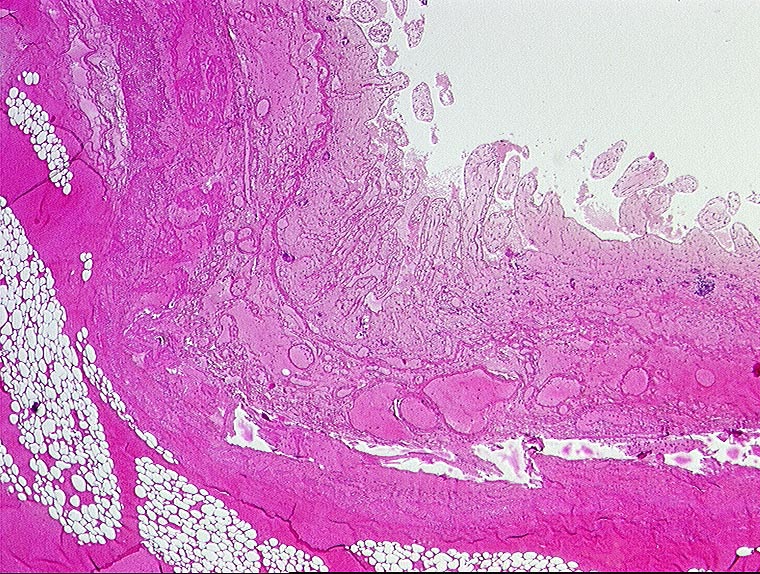

PathoPic ID 431 - embolischer Mesenterialinfarkt

embolischer Mesenterialinfarkt

vaskulär / Durchblutungsstörung

Dünndarm

Kardiovaskuläres System

Hämorrhagische Nekrose der Darmwand.

Alter Myokardinfarkt Parietalthrombus. Frische Emboli in eröffneten Ästen der Arteria mesenterica superior.

Histologie